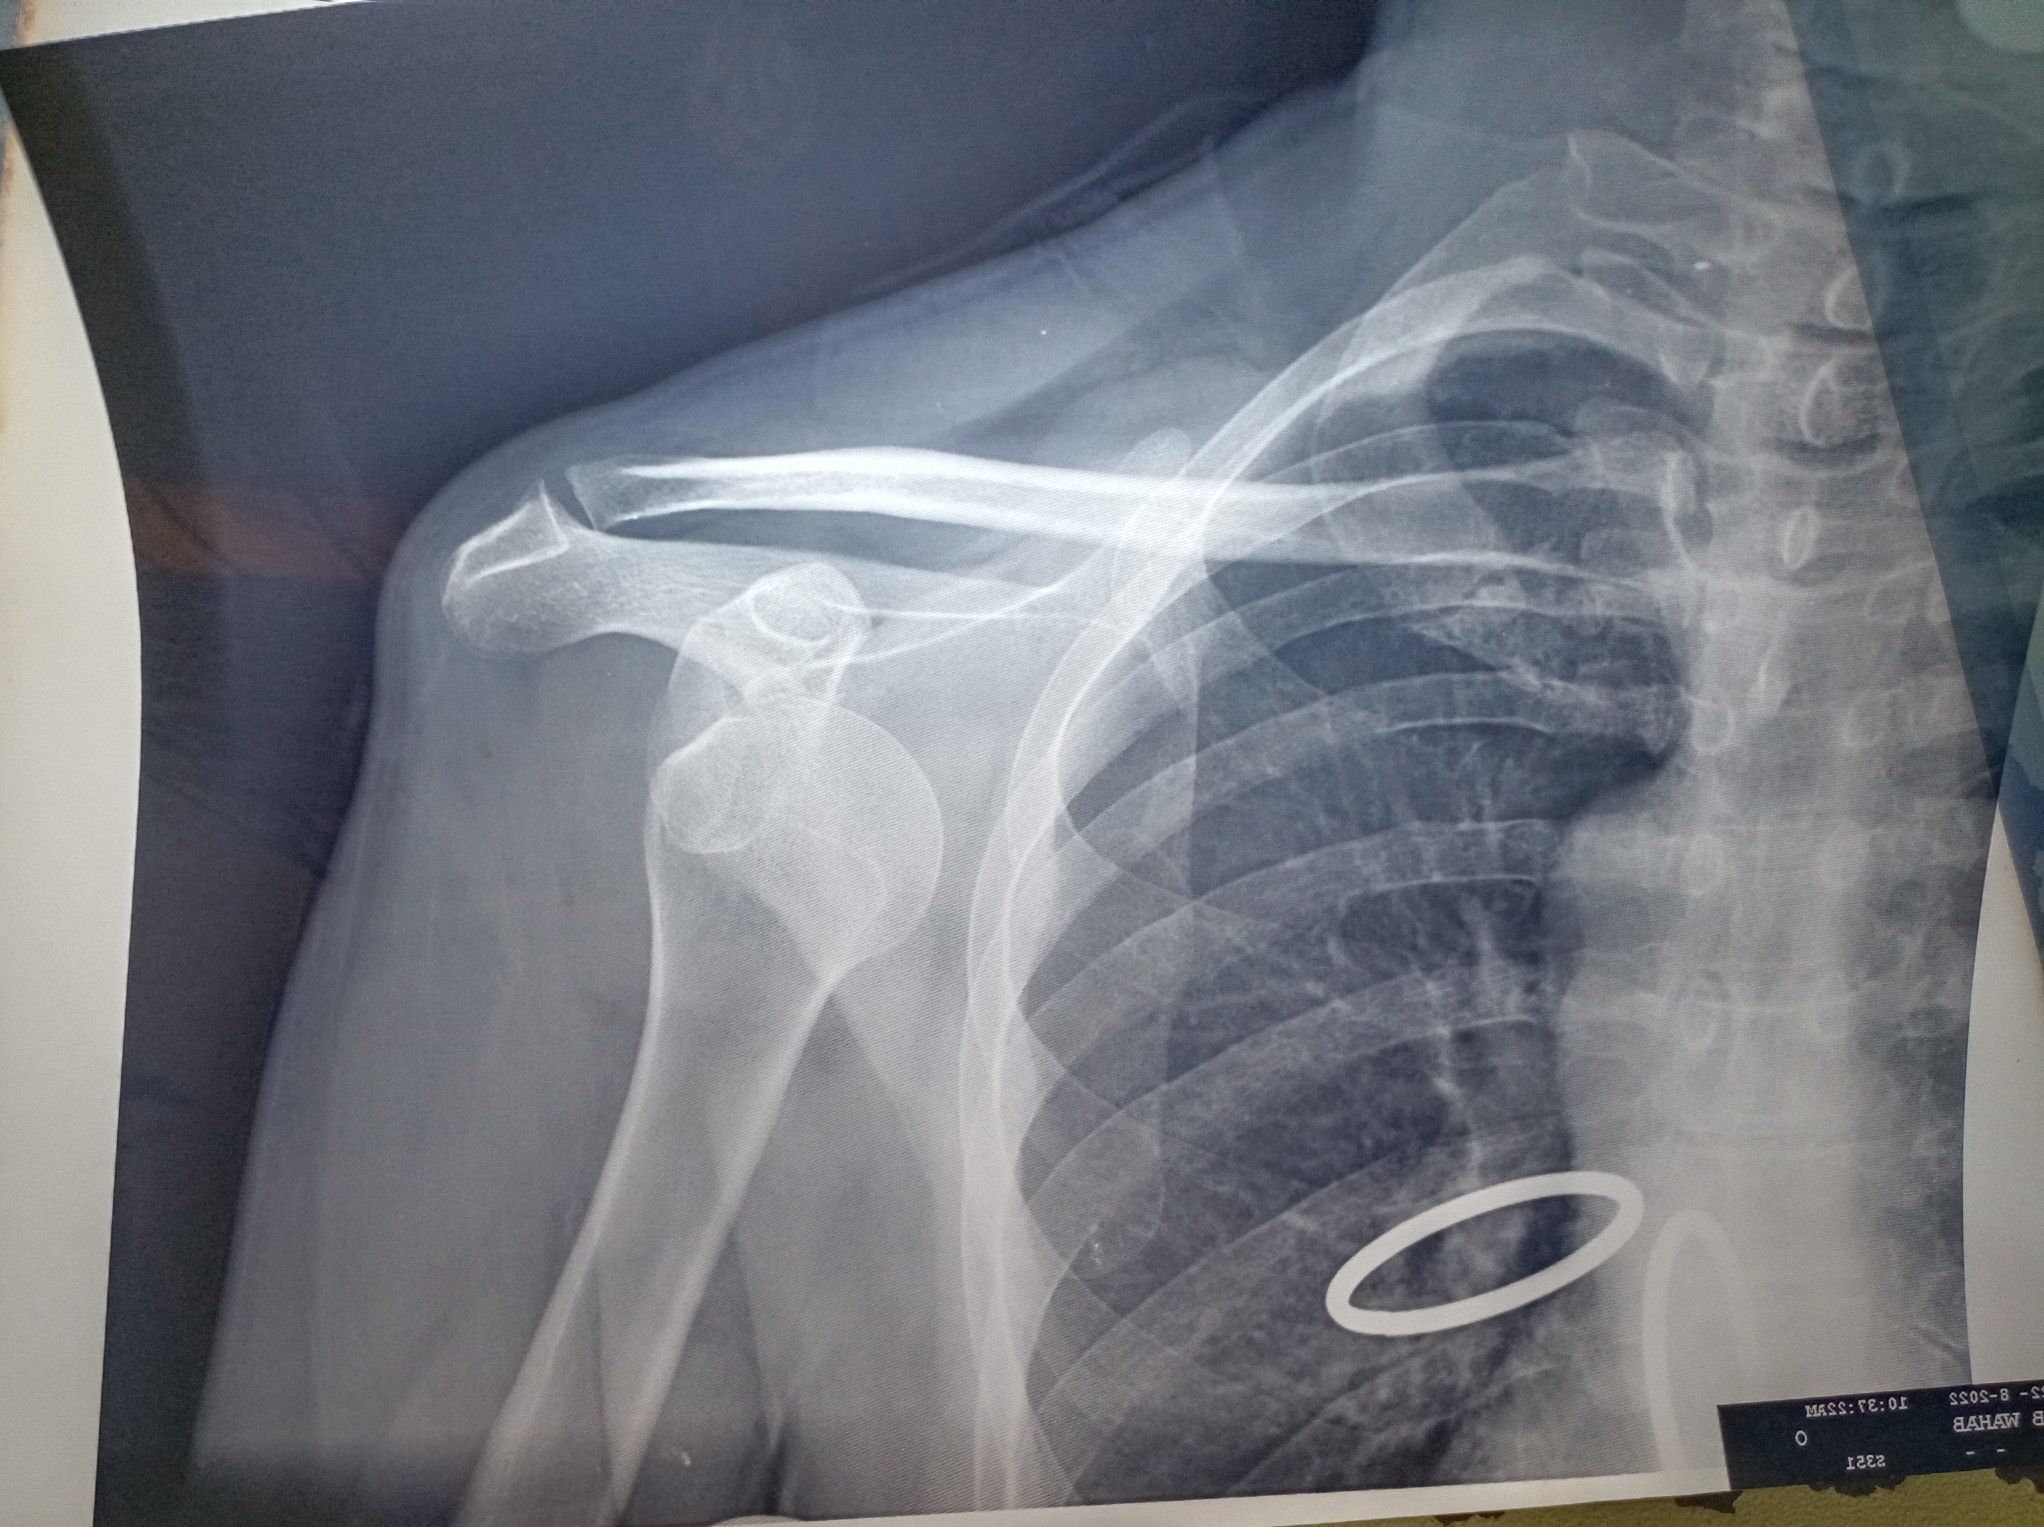

Shoulder dislocation

Anterior